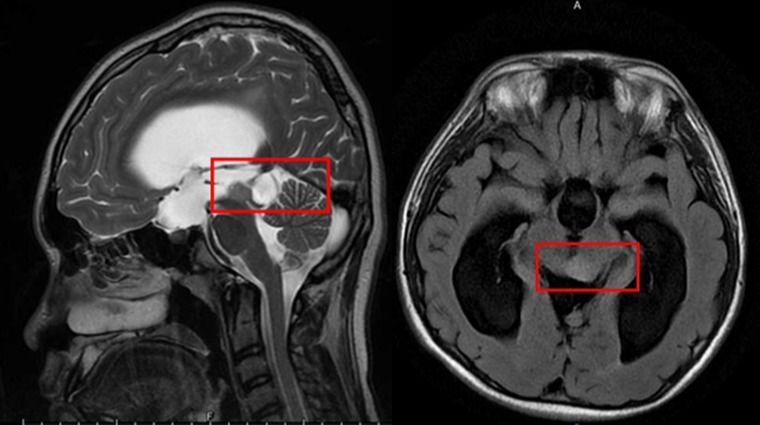

▲15歲男童日前因頭痛不適昏倒,經腦部核磁共振檢查確診為水腦併中腦腫瘤(紅框處)。(圖/台大醫院新竹分院提供)

【NOW健康 陳盈臻/新竹報導】1名15歲男童日前因頭痛不適昏倒,被家人緊急送往急診,經診斷疑為水腦合併癲癇,施以抗癲癇藥物治療。但男孩父母對癲癇病情仍有疑慮,故改往台大醫院新竹分院小兒神經科門診就醫。透過檢查,發現男孩眼動受限,眼睛無法往上看及往外側注視,醫師問診發現,他從小學4年級就開始頭痛,且因眼動受限而時常跌倒。經腦部核磁共振檢查確診為水腦併中腦腫瘤,立即安排手術治療。